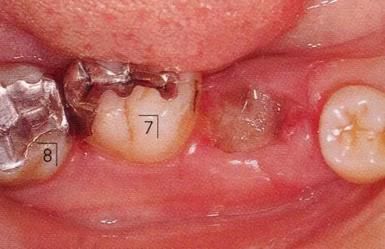

360截圖20170422101945505.jpg

▲圖9-1,2

▲圖9-1 預(yù)定進(jìn)行正畸治療的患者,下頜磨牙區(qū)的右下6,7牙根接近,并在右下7遠(yuǎn)中存在垂直性骨組織缺損。對牙體狀況、牙周組織、咬合情況進(jìn)行診斷后制定出的治療方案為:將右下6拔除,對右下7遠(yuǎn)中的骨組織缺失進(jìn)行再生療法。

▲圖9-2 同部位X光片。右下6遠(yuǎn)中存在牙根接近,較深的骨組織缺損以及II度根分叉病變,所以將其拔除。